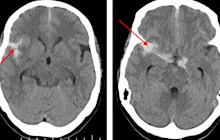

家住平马镇,65岁的言爷爷因突发头晕呕吐3小时到田东县中医医院脑病科住院治疗,行头颅CT扫描检查结果提示“蛛网膜下腔出血”,为患者进一步行脑血管造影检查时发现了一枚“不定时炸弹”一右侧颈内后交通宽颈动脉瘤(4.0*6.0mm)。动脉瘤累及了重要血管分支,极容易破裂出血。颅内动脉瘤是指脑动脉内腔的局限性异常扩大造成动脉壁的一种瘤状突出,多因脑动脉管壁局部的先天性缺陷和腔内压力增高的基础上...发布时间:2024-08-12

2024年6月19日,家住平马镇的黄阿姨和家人在家中休息,下午15点左右,黄阿姨突然感觉头晕目眩,反胃,恶心呕吐,视物旋转,伴头痛,家人立即送至田东县中医医院急诊科,急诊医生接诊后,考虑脑血管意外,于是立即启动卒中急救绿色通道。急诊头颅CT显示蛛网膜下腔出血,建议行CT血管成像(CTA)进一步检查排除动脉瘤破裂出血。入院时头颅CT出血灶经田东县中医医院脑病科技术主任龙少根副主任医师会诊后,...发布时间:2024-07-19